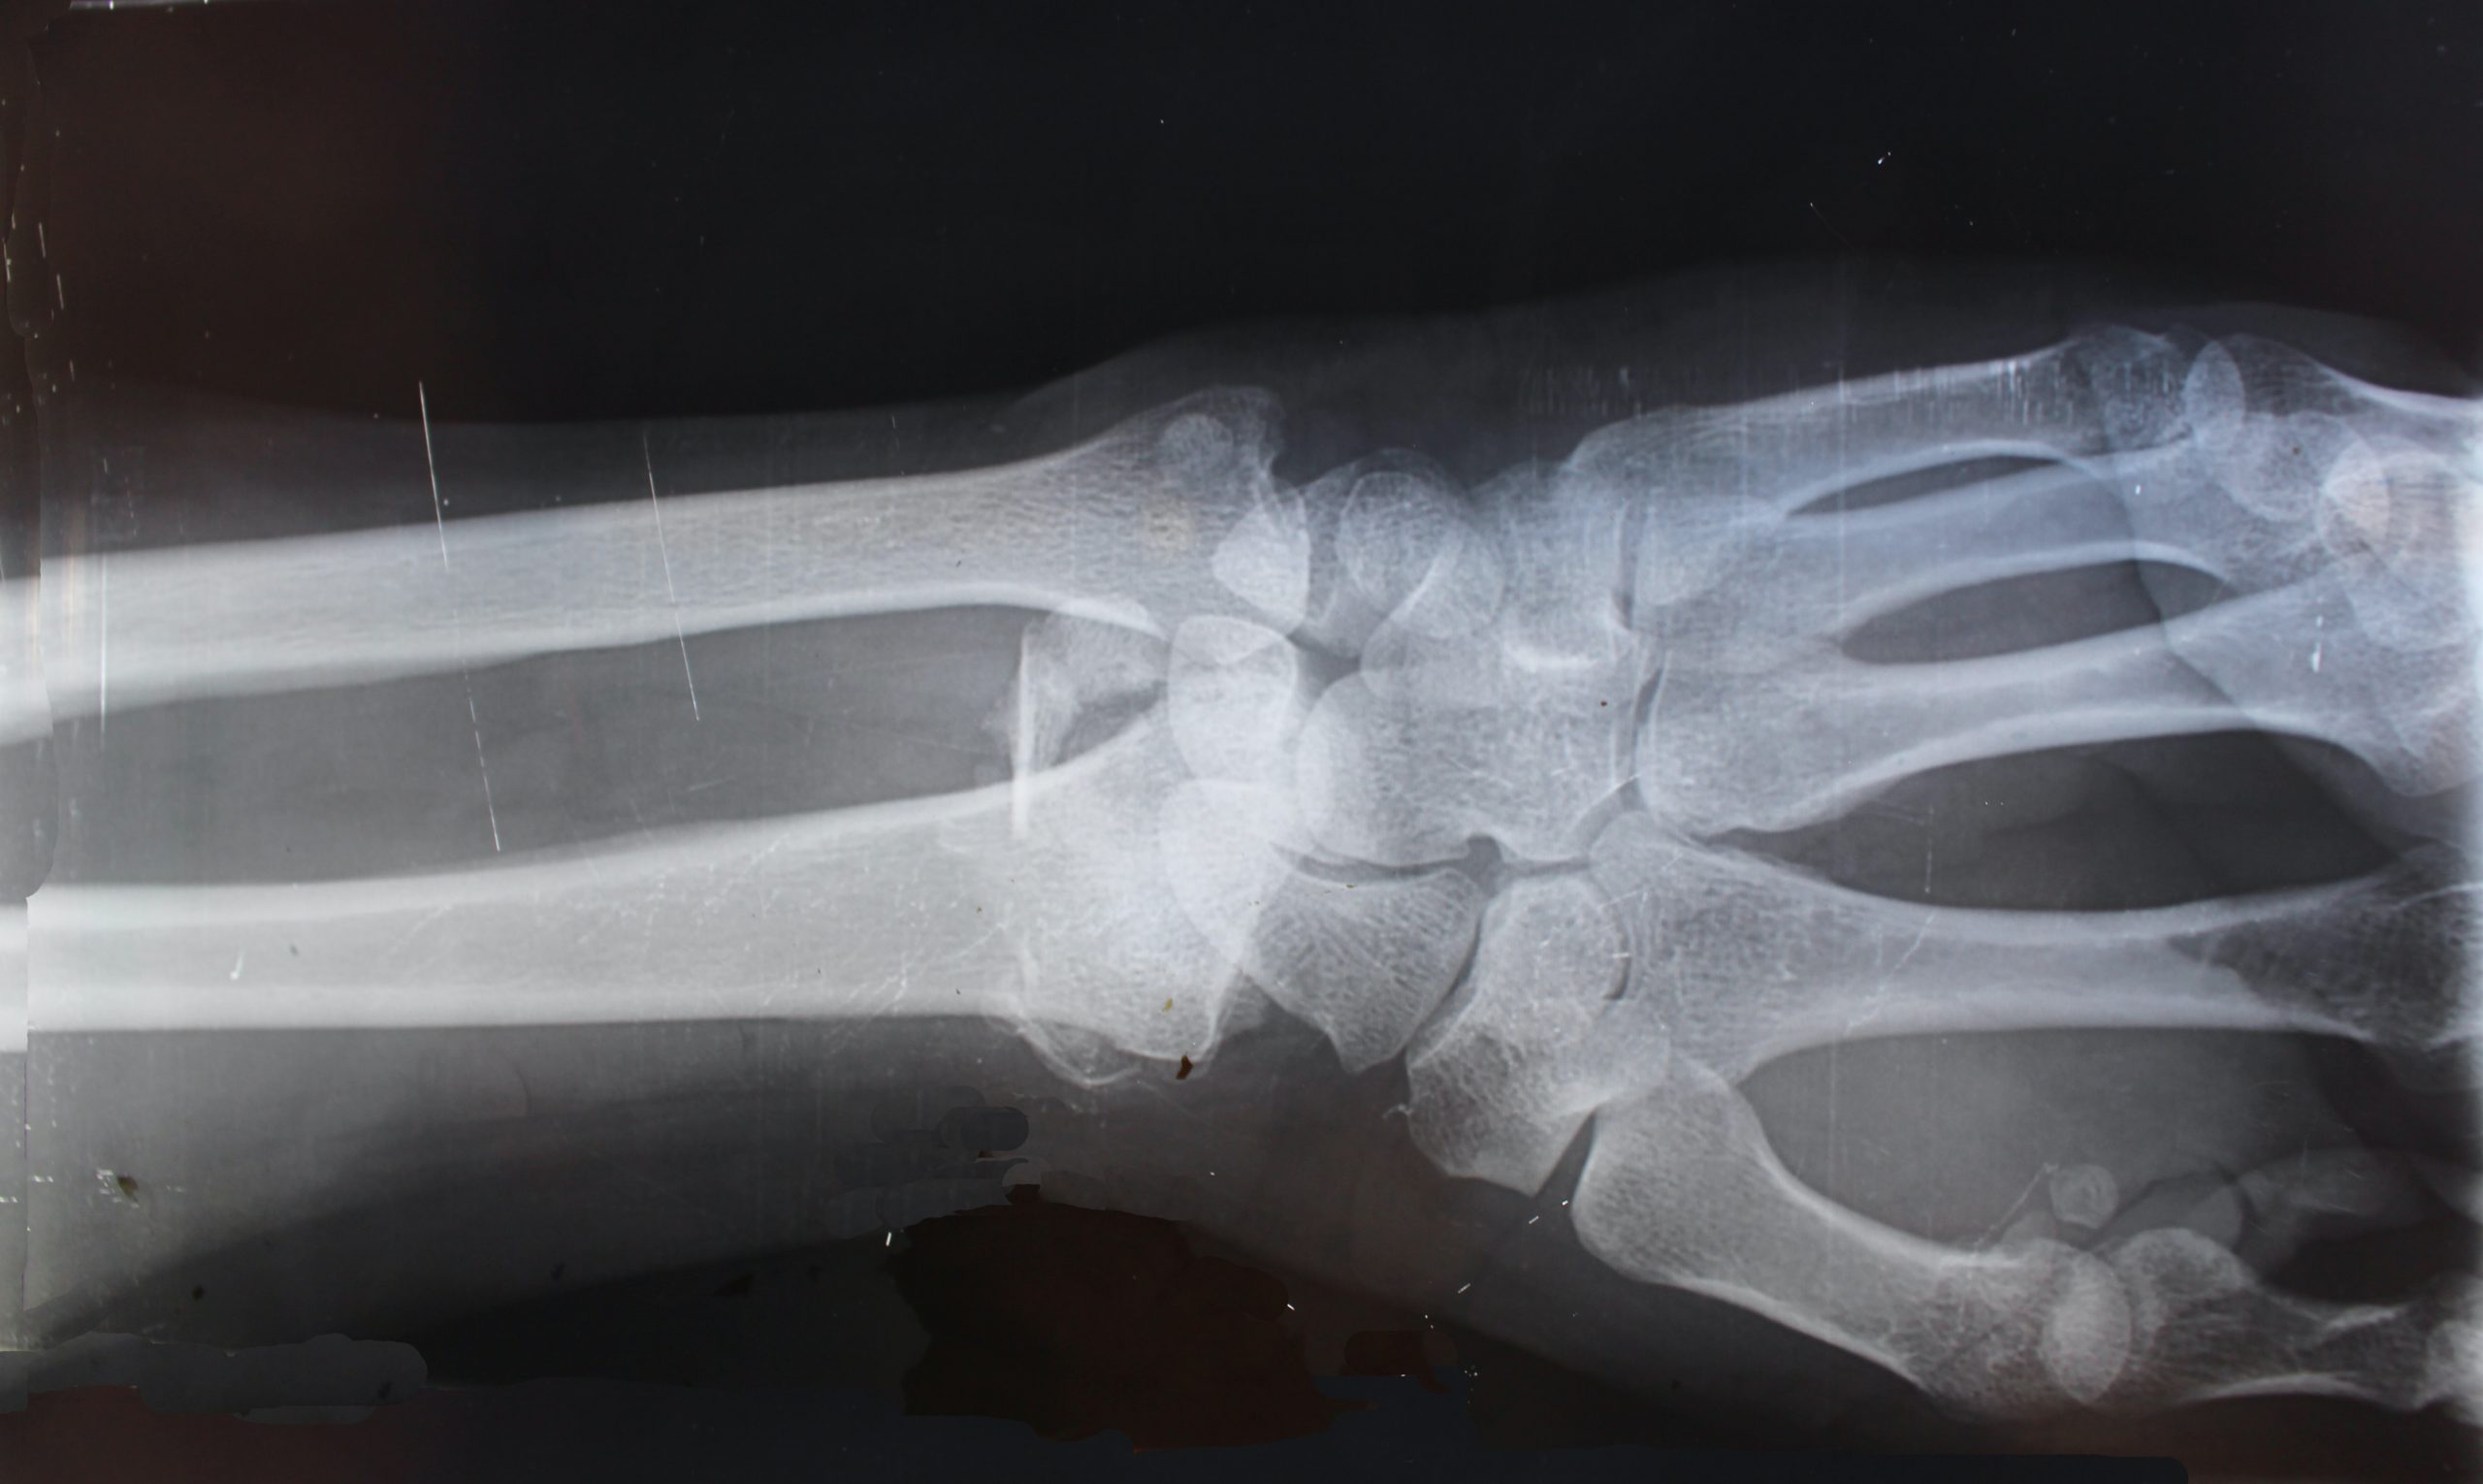

After the stabilization, patient’s clinical status should be established. Then to identify the type of fracture, minimum two x-rays of the glenohumeral joint should be taken at right angles to each other are required. Three x-rays of the trauma-series will be better particularly for preoperative planning of B and C fractures.

If there is any susceptibility of tuberosity fractures, x-rays in external and internal rotation of the humerus may be useful. If these standardized x-rays do not help in proper assessment of the features of main fracture, displacement of fragments, of articular damage, and soft-tissue involvement then CT will be useful. To classify the fracture, and to decide the surgical procedure or prognosis, it will be necessary to determine whether the fracture runs through the anatomical or surgical neck.